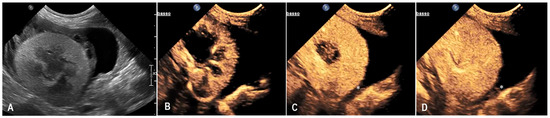

3.2. Case 2